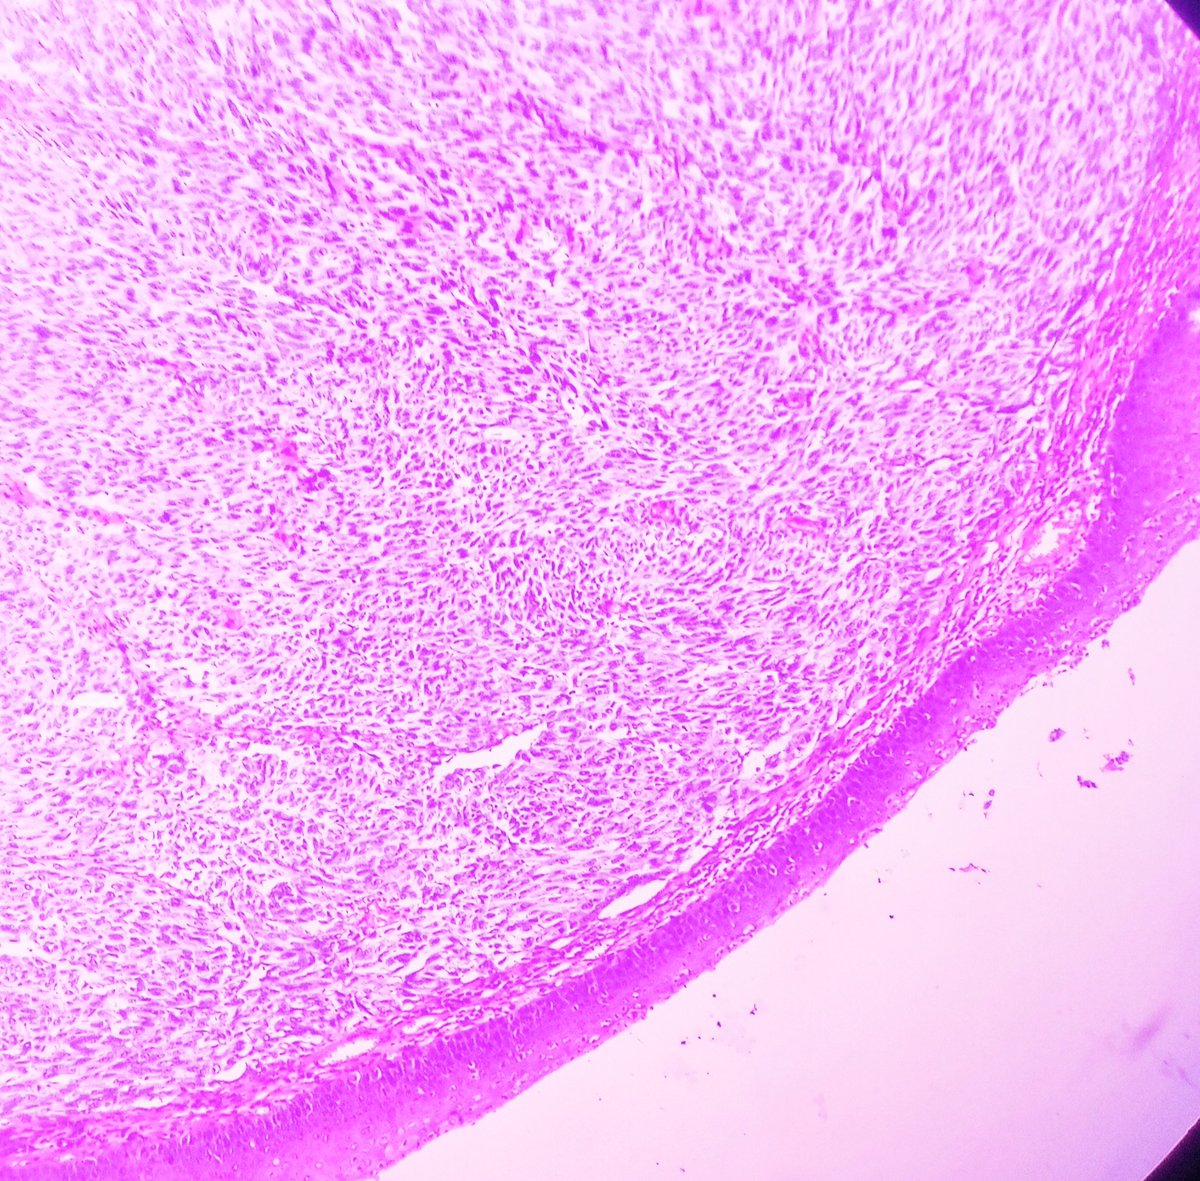

Ulcerated Anal Amelanotic Melanoma in 60y/M. #APCON2022 #APCON2022PathTweet GI James Padma Priya J Kenny De Gracia T. Archana bhat Aditya Agnihotri 🇮🇳 Vijay Shankar S Annie A. Wu, MD, PhD Olaleke Folaranmi Daisy Maharjan Dante Aswathy Menon Ananthvikas Dr Anila Sharma Frank Ingram, MD Arunima Deb, MD #pathology #PathTwitter